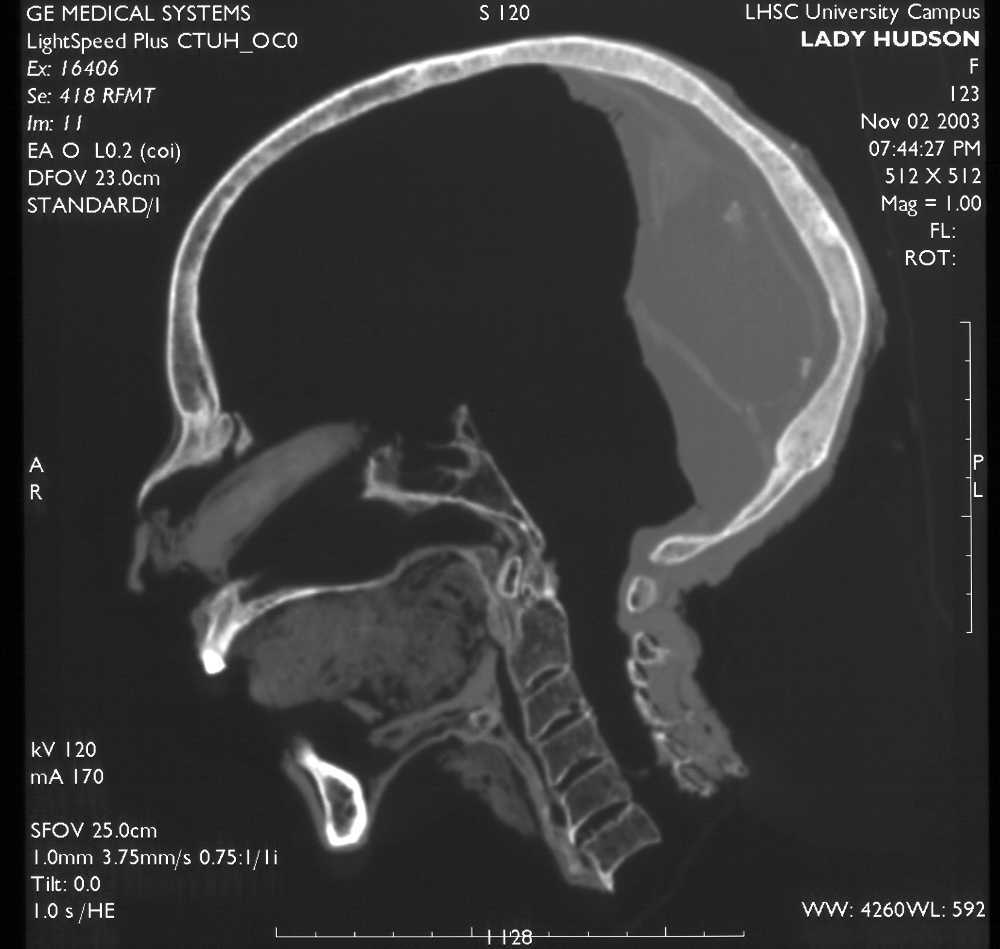

A CT slice through the midline of the head of a mummy—Lady Hudson—showing that her brain was removed through her nose and resin poured into the rear of the skull. Image courtesy of Andrew Nelson, University of Western Ontario.